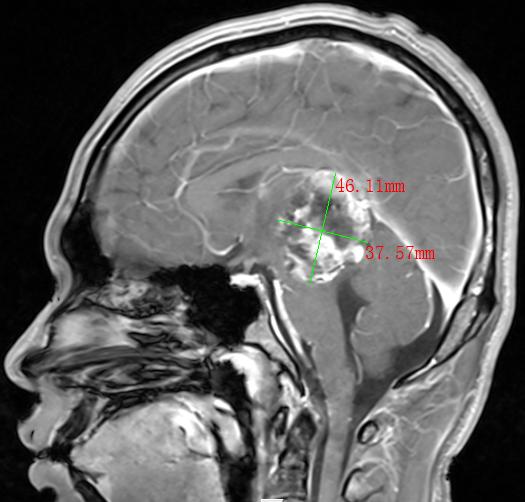

2022年,30多岁的张先生和40岁岁的李先生,均出现神志模糊或不清,并有反复癫痫发作的情况,经过当地医院检查,张先生和李先生分别诊断为松果体肿瘤、间变型星形细胞瘤术后复发并多发种植转移,两人颅内肿瘤直径分别达4.0cm和9.8cm。由于两人颅内肿瘤太大,辗转多家医院求医未果,正当两家人要放弃的时候,听朋友介绍瑞康医院射波刀治疗恶性肿瘤的效果非常不错,两家人怀着试一试的心态来到瑞康医院肿瘤科一区。

松果体区肿瘤MRI影像

间变型星形细胞瘤术后复发并多发种植转移MRI影像